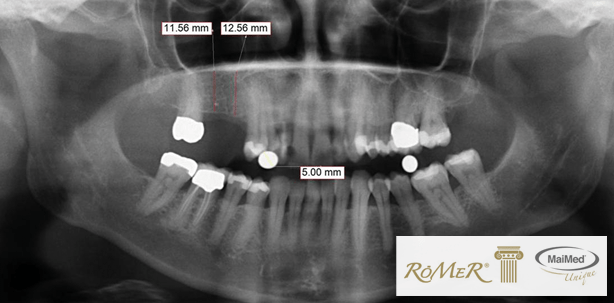

Eine Neuentwicklung beschleunigt künftig die röntgenologische Diagnostik von Zahnärzten und Implantologen. Die Röntgen-Mess-Rolle RöMeR® nach Dr. Middelmann macht die aufwändige Herstellung von Röntgen-Mess-Schablonen bei Panoramaaufnahmen des Kiefers (Orthopantomogramm, kurz OPG) künftig überflüssig.

Diese Innovation besteht aus einem dentalen Baumwollträger, in den eine Metallkugel als Referenzkörper eingebettet wurde. Anhand der vordefinierten Größe des Referenzkörpers von fünf Millimetern können bereits beim ersten Termin schnell und kosteneffizient die räumlichen Gegebenheiten (vertikale Relationen, interalveoläre Distanzen, Knochenprofile und -angebot) vermessen werden. Der Abdruck des Kiefers, die Erstellung eines Modells und die Anpassung einer Röntgenschablone im Dentallabor entfallen künftig. „Unsere Neuentwicklung schafft eine Win-Win-Situation für Zahnarzt und Patient: geringer Arbeitsaufwand und Zeitgewinn für den Mediziner und niedrigere Kosten für den Patienten“, erläutert Holger Harms, Geschäftsführer der MaiMed GmbH.

Somit sind Zahnärzte – wenn es um die Beurteilung von interalveolären Distanzen, vertikalen Dimensionen, Knochenprofilen oder räumlichen Abständen zu Nerven und Kieferhöhlen geht – bei OPG-Aufnahmen auf röntgendichte Messkörper definierten Durchmessers angewiesen, um diese Informationen zu berechnen. Bevor ein Röntgenbild mit Referenzkörper erstellt werden kann, muss bisher laborseitig eine Röntgen-Mess-Schablone angefertigt werden, um den Messkörper adäquat im Mund des Patienten fixieren zu können. Bis mit der definitiven Versorgung begonnen werden kann, sind so meist drei Patiententermine verstrichen, ein weiteres OPG sowie zusätzliche Kosten für die Laborleistungen in Höhe von 150–180 Euro nötig. Alle Versuche von Zahnärzten, die Metallkugeln anderweitig im Mund des Patienten zu fixieren (z.B. mit Wachs) scheiterten bislang. „Das ist nicht nur unzulässig und verstößt gegen die Sorgfaltspflicht, sondern es ist auch extrem gefährlich“, sagt Dr. Heinrich Middelmann, Zahnarzt und Implantologe aus München, der die Röntgen-Mess-Rolle entwickelt hat. „Der Patient kann seine Zähne beschädigen, die Metallkugel verschlucken oder sie schlimmstenfalls aspirieren“.

Die Anwendung ist denkbar einfach. Ein Paar Röntgen-Mess-Rollen werden vor dem Röntgen rechts und links auf den Kauflächen der unteren Backenzähne positioniert. Nach dem Röntgen werden die Röntgen-Mess-Rollen entfernt und entsorgt. Dieser Prozess ist problemlos an die Röntgenassistenz delegierbar.